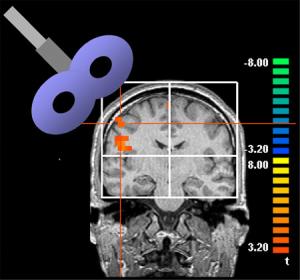

rTMS is applied with an electromagnetic coil in the shape of a figure-eight, placed on the scalp directly over the targeted portion of the brain. Short bursts of a strong magnetic pulse stimulate electrical currents within. Sensory input from each region of the body is represented on the surface of the brain, and the location of any region--in this case, the right index finger--can be mapped to allow precise targeting of the rTMS. The authors adjusted the strength of the magnetic field to just below that which triggered a sensory response in the finger, and then applied intermittent pulses of stimulation over the course of about ten minutes.

The authors used functional magnetic resonance imaging (fMRI) to see how the brain changed in response to the stimulation. They found that the region representing the index finger got larger, and that the degree of increase in any one subject corresponded to the degree of increased sensitivity in that same subject. As the sensory effect faded, so too did the fMRI changes. Thus, the cortex itself undergoes changes as a result of rTMS.